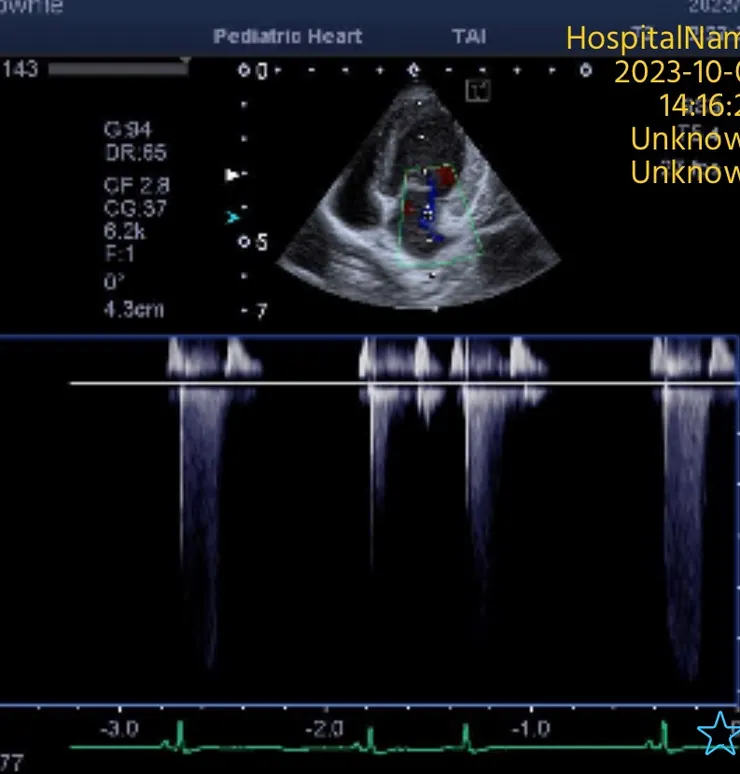

➡️心臟超音波可以幫助我們看到左心房的擴張或是腱所斷裂瓣膜退化等, 詳細一點的話也可以評估左心房的壓力用來輔助我們判斷心因性肺水腫的可能性, 但心臟超音波無法看到肺臟狀況。所以最終還是會需要用xray 去看肺部的狀況, 證實有肺積水。

心臟超音波 二尖瓣退化

心臟超音波二尖瓣繞流